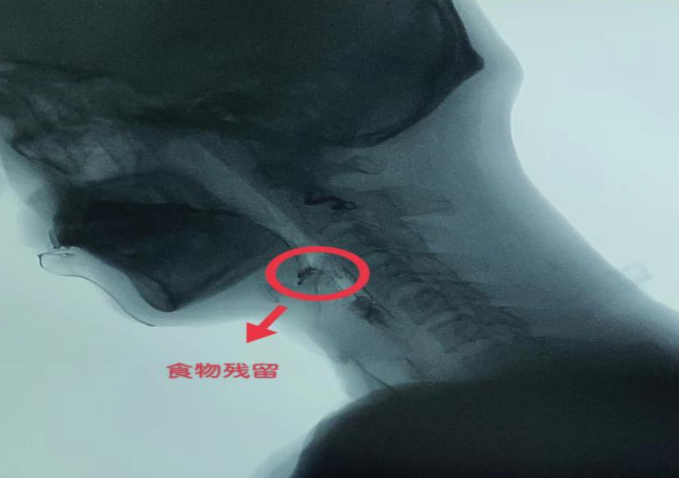

在我们日常生活中有各种形形色色的美食,对于我们来说,能够随心所欲地吃是多么的幸福呀!但是很多脑卒中患者却不能像常人那样尽情享用美食。随着我国人口老龄化程度的增加,脑卒中患者发病率呈明显上升趋势,其中吞咽功能障碍为脑卒中最常见的并发症之一,其中吞咽障碍又常引起误吸呛咳、营养不良,导致感染风险增加,严重影响患者的生活质量。吞咽功能障碍是由于下颌、双唇、舌、软腭、咽喉、食管括约肌、食管本身的功能受损,不能安全有效地把食物经口腔送到胃内取得足够营养和水分的进食困难。为了解决他们的摄食—吞咽障碍问题,让他们重新享受人间美味,重建获取食物的渠道,重新的健康起来,是我们的重任。选择合适食物、餐具及正确的喂食方法,能有效地防止呛咳误吸等并发症的发生,并能使患者得到足够的营养,具备了自身的应有体力和抗病能力,增加了患者生活信心。长辈经常教育孩子,吃饭的时候不要说话,说话容易引起呛咳,很多人不知道原因是什么?那是因为我们在说话或呼吸时,会厌组织向上,气道打开,这时我们如果吞咽食物,会厌组织来不及关闭,食物就会进入气管,引起呛咳。因此,在吃饭的时候一定要在一个安静的环境,避免与他人交谈。(1)卧位进食姿势 一般取躯干30°,头部前倾,偏瘫侧肩背部用枕垫起,喂食者位于患者健侧,食物不易从口中漏出,利于食物向舌部运送,减少逆流和误咽,每日逐渐抬高床头直至能维持独立坐位。禁止平卧进食;(2)坐位进食姿势 取坐直、头稍前倾,身体可倾向健侧30°,偏瘫侧上肢放于餐桌上。a:匙:应选用柄粗、柄长、匙面小、难以粘上食物、边缘钝滑的匙,容量5-10ml。(1)选择原则:以密度均匀 , 黏性适当、不易松散,通过咽部和食管容易变形的,不易粘在口腔或食道粘膜上的食物。如鸡蛋羹、增稠剂调配过的食物。避免食用有碎屑的糕饼类食物。(3)食物的种类的选择包括:糊状食物、稀流质 、浓流质 、烂饭等。(4)不同性状食物的调配:在临床实践中,吞咽障碍患者首选糊状食物。亦可根据吞咽障碍影响吞咽器官的部位,因地制宜选择适当食物。不同质地的食物根据需要,可调制成不同形态。即适于吞咽的每次摄食量,先以3-4ml开始(半勺),然后酌情增加至1勺大小为宜。一般正常人每口量:流质1-20ml、果冻5-7ml、糊状食物3-5ml、肉团平均为2ml。过多:食物很难通过咽喉,导致残留增多,加大误咽的危险。进食时应把食物放在口腔最能感觉食物的位置,最好把食物放于健侧舌后部或健侧颊部,这样有利于食物的吞咽。以较常人缓慢的速度进行摄食,咀嚼和吞咽,一般每餐进食的时间控制在45分钟左右为宜。每次食物后,在反复做几次空吞咽时食物全部吞下然后再进食。让患者每次吞咽食物后饮少许水(1-2ml),这样既能激发吞咽反射,又能清除残留物。颈部后仰时会厌谷变窄,可挤出残留物,随后低头并做吞咽动作,反复数次,可清除咽下残留物。让患者做向左、右侧的点头样吞咽 ,可清除两侧梨状隐窝的残留。对于年龄较大的患者,平时在进食过程中,照顾者在喂食时也可作出以下几点提醒~(1)言语示意:照顾者在患者边进食时边说“吞”来提醒患者。(2)手势示意:照顾者指着自己的嘴巴以提醒患者在吞咽时保持嘴唇闭紧。1、进食需要在清醒的状态下进行,神志不清、不合作者勿喂食,如进食时容易疲倦,宜少食多餐;6、进食后不能立即平卧,可保持舒适的半卧位或坐位30分钟以上。康复医学科是成都市级重点中医专科建设单位,区级医学重点专科,四川省康复社保定点单位,成都中医药大学附属医院专科联盟单位。国家专利6项,主持省市区级科研课题4项。医务人员28名,中高级职称10人,硕士研究生4名。中国工程院院士石学敏国医大师学术继承人1名,成都市名中医1名,龙泉驿区名中医1名。